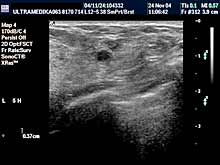

- ako postoji promena i mikrokalcifikacija obavezna je primena: 3D Sono CT i 3D CPA i Broad

band-CD i CPD,

Tačna lokalizacija promene se vrši uz pomoć PANORAMA moda.

- XRes,

- Ciljana biopsija tumorske promene pod kontrolom ultrazvuka.